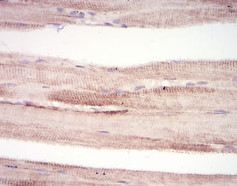

MuRF1 Mouse Monoclonal antibody[7B8E1]

This gene encodes a member of the RING zinc finger protein family found in striated muscle and iris. The product of this gene is an E3 ubiquitin ligase that localizes to the Z-line and M-line lattices of myofibrils. This protein plays an important role in the atrophy of skeletal and cardiac muscle and is required for the degradation of myosin heavy chain proteins, myosin light chain, myosin binding protein, and for muscle-type creatine kinase.

Immunogen:    Synthesized peptide of human MuRF1 (AA: 293-304).

IHC    1/200 - 1/1000